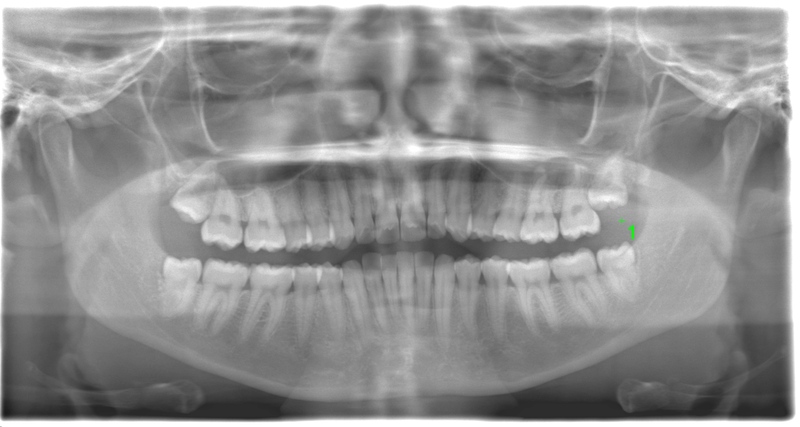

CASE 17

基本情報

| 年齢・性別 | 18歳・男性 |

|---|---|

| 主訴 | 矯正を開始する前に左下と左上の親知らずを抜きたい |

| 抜歯期間 | 約1時間 |

| 抜歯費用 | 1本22,000円×2本 合計44,000円 (2022年10月現在) |

| 抜歯内容 | 完全埋伏抜歯 |